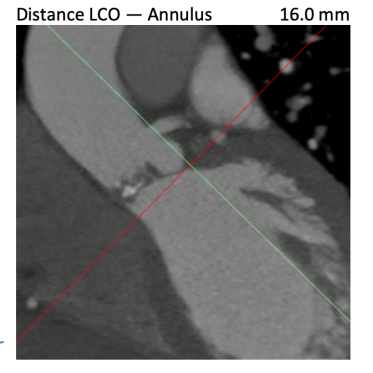

根据FEops报告上的左右冠脉CT截面得知RCA Height:16.0mm、LCA Height:16.0mm,冠脉阻塞风险比较低,通过植入前后的3D模型对比瓣叶形态可以进一步验证。